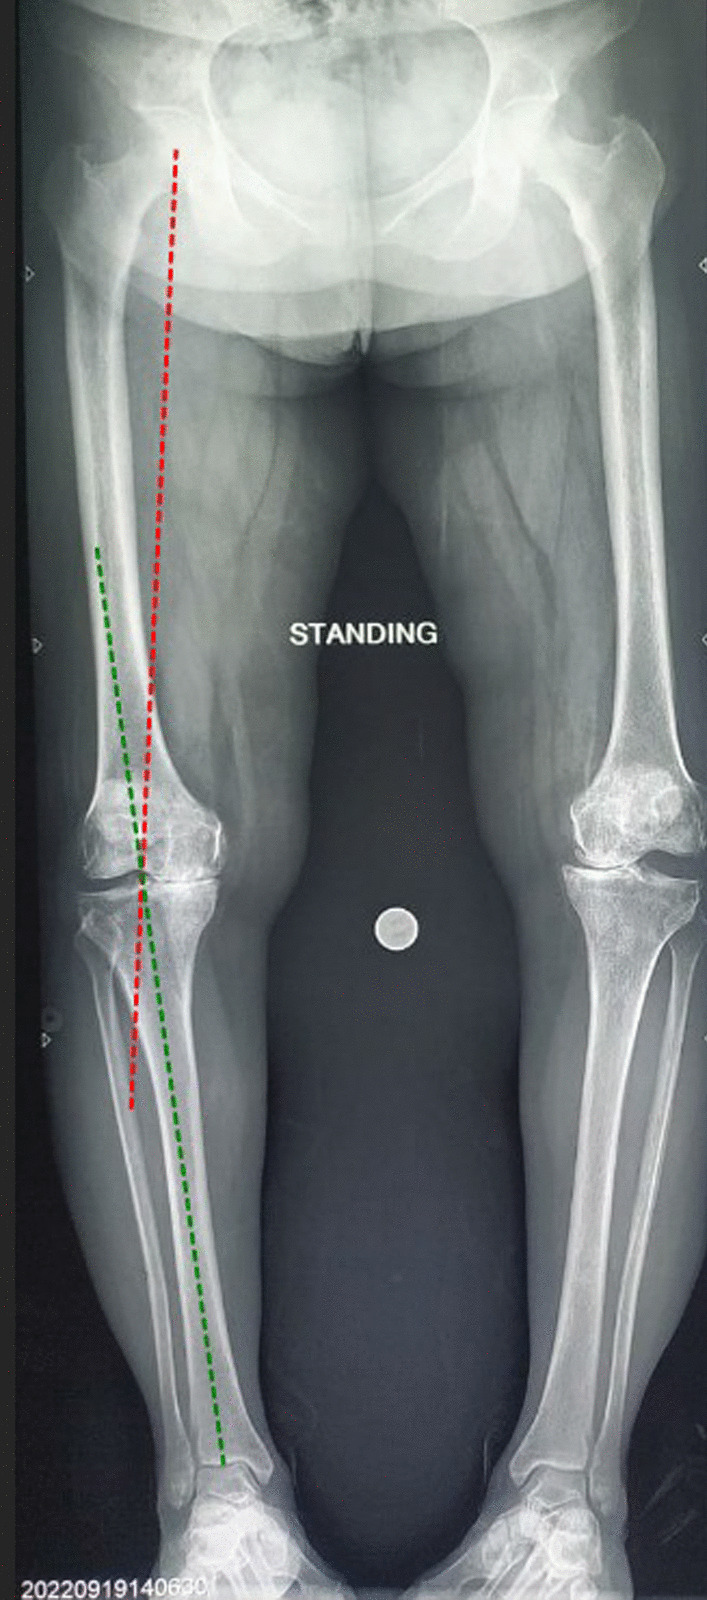

Methods: The prospective observational study included 61 patients (122 knees) undergoing simultaneous bilateral TKA (mechanical alignment). Tibio-talar angle(TTA), tibial Anterior Surface angle (TAS), lateral distal tibial angle (LDTA), talar-tilt angle (TT), anatomical talocrural angle (aTC), ground surface and distal tibial plafond angle (GP), ground surface and an upper surface of talus angle (GT)and tibial plateau and tibial plafond angle (PP) were measured on long-film radiographs to look for changes in the ankle, whereas functional assessment was done using American Foot and Ankle Society (AOFAS), Foot and Ankle Disability Index (FADI), and Forgotten Joint (FJS-12) scores. Patients were sub-grouped based on the Hip-Knee-Ankle (HKA) axis, and the effect of the severity of knee varus on the ankles after TKA was also analyzed. The minimum follow-up was 6 months.

Results: A significant decrease in the tibial plateau-tibial plafond (PP), ground-tibial plafond (GP), and ground-talar dome (GT) angles was noted after TKA (p-value < 0.05). Postoperative functional parameters were comparable to the preoperative status except for FADI, which significantly improved (p-value-0.03). Sub-group analysis based on the severity of knee varus (HKA) revealed GT to be most significantly reduced (p-value-0.036), while the talar tilt (TT) increased (p-value-0.044). Functional outcomes of the ankles clinically improved with the correction of severe knee varus after TKA. At a mean follow-up of 13.2 months post-TKA, 7 out of 61 (11.4%) patients complained of post-TKA ipsilateral ankle pain.

Conclusion: Mechanically aligned bilateral TKA in severe varus deformity of the knee significantly decreases the GT angle but increases the varus tilt of the talus with lateral talar incongruency and under-coverage. Although the acute correction of severe knee varus deformity aligns the tibia more neutrally, resulting in an overall clinically evident improvement in ankle functional outcome, the increased varus talar tilt remains a deep concern.